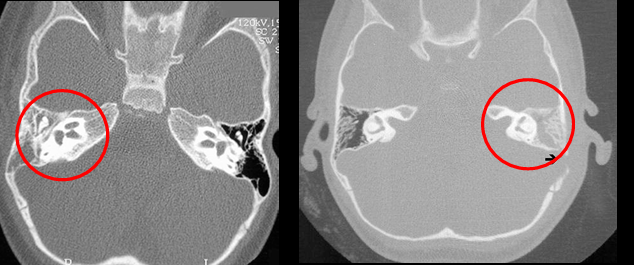

Tc en otitis media

Masa bien definida en oído medio (densidad intermedia)

Erosiones osiculares o laberínticas

Asociación a mastoiditis